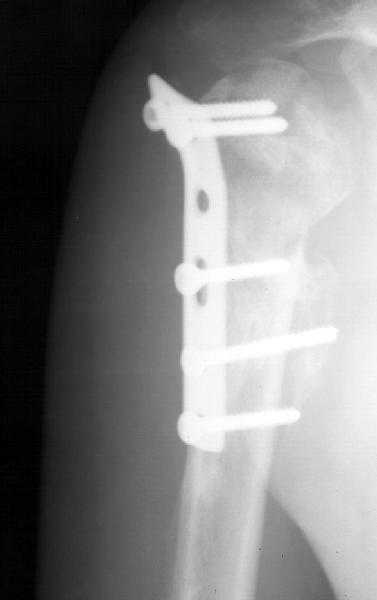

Мужчина 25 лет 16 августа 2002 г. в автоаварии получил перелом шейки плеча (снимок 1); 5 сентября в городской больнице выполнен остеосинтез пластинкой (снимок 2).К настоящему времени попал к нам на разработку ввиду выраженной контрактуры плечевого сустава. В течение последнего месяца беспокоят умеренные боли в области плечевого сустава, усиливающиеся при разработке, еще и торчит край пластинки. Нынешняя рентгенологическаякартина на снимках 3 и 4. Головка плеча уменьшается, сращение сомнительное.Кроме удаления пластинки, что еще на сегодня целесообразно сделать?Заранее спасибо.

2.Пластинка , на мой взгляд, худшее решение для перелома шейки плеча. Сама пластинка слишком груба и массивна, целая слесарня в очень чувствительной для повреждений суставе.